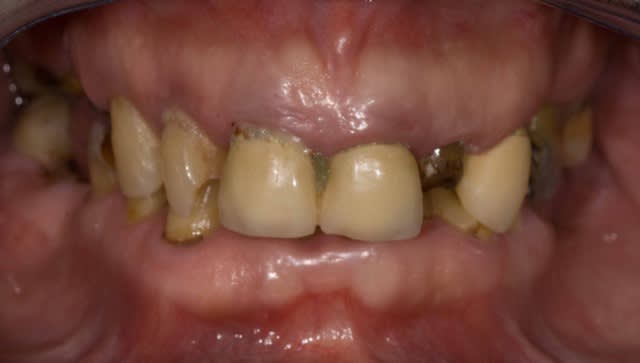

1) Patient qui semble bruxoman

2) Perte du calage postérieur donc propulsion de la mandibule pour rechercher de la proprioception avec les dents antérieures ( bonne change pour le remettre en relation centrée !).

3) Augmentation de DV ou elongation coronaire semble nécéssaire

4) Vu le parodonte du Patient et le sexe masculin .Il doit avoir des masseters comme des biceps

5) Le patient ne semble pas avoir une exigence esthétique enorme

6) Tu vas faire des stellites avec attachements qui vont encore plus augmenter la tension sur les cérams.

Si tu cherches les limites mécaniques des reconstitutions fibrées , crois moi tu vas dans le mur direct. Si tu poses la question juste pour faire polémique sache que c'est débile car face a un cas comme ca meme ma grand mere poserait des IC.